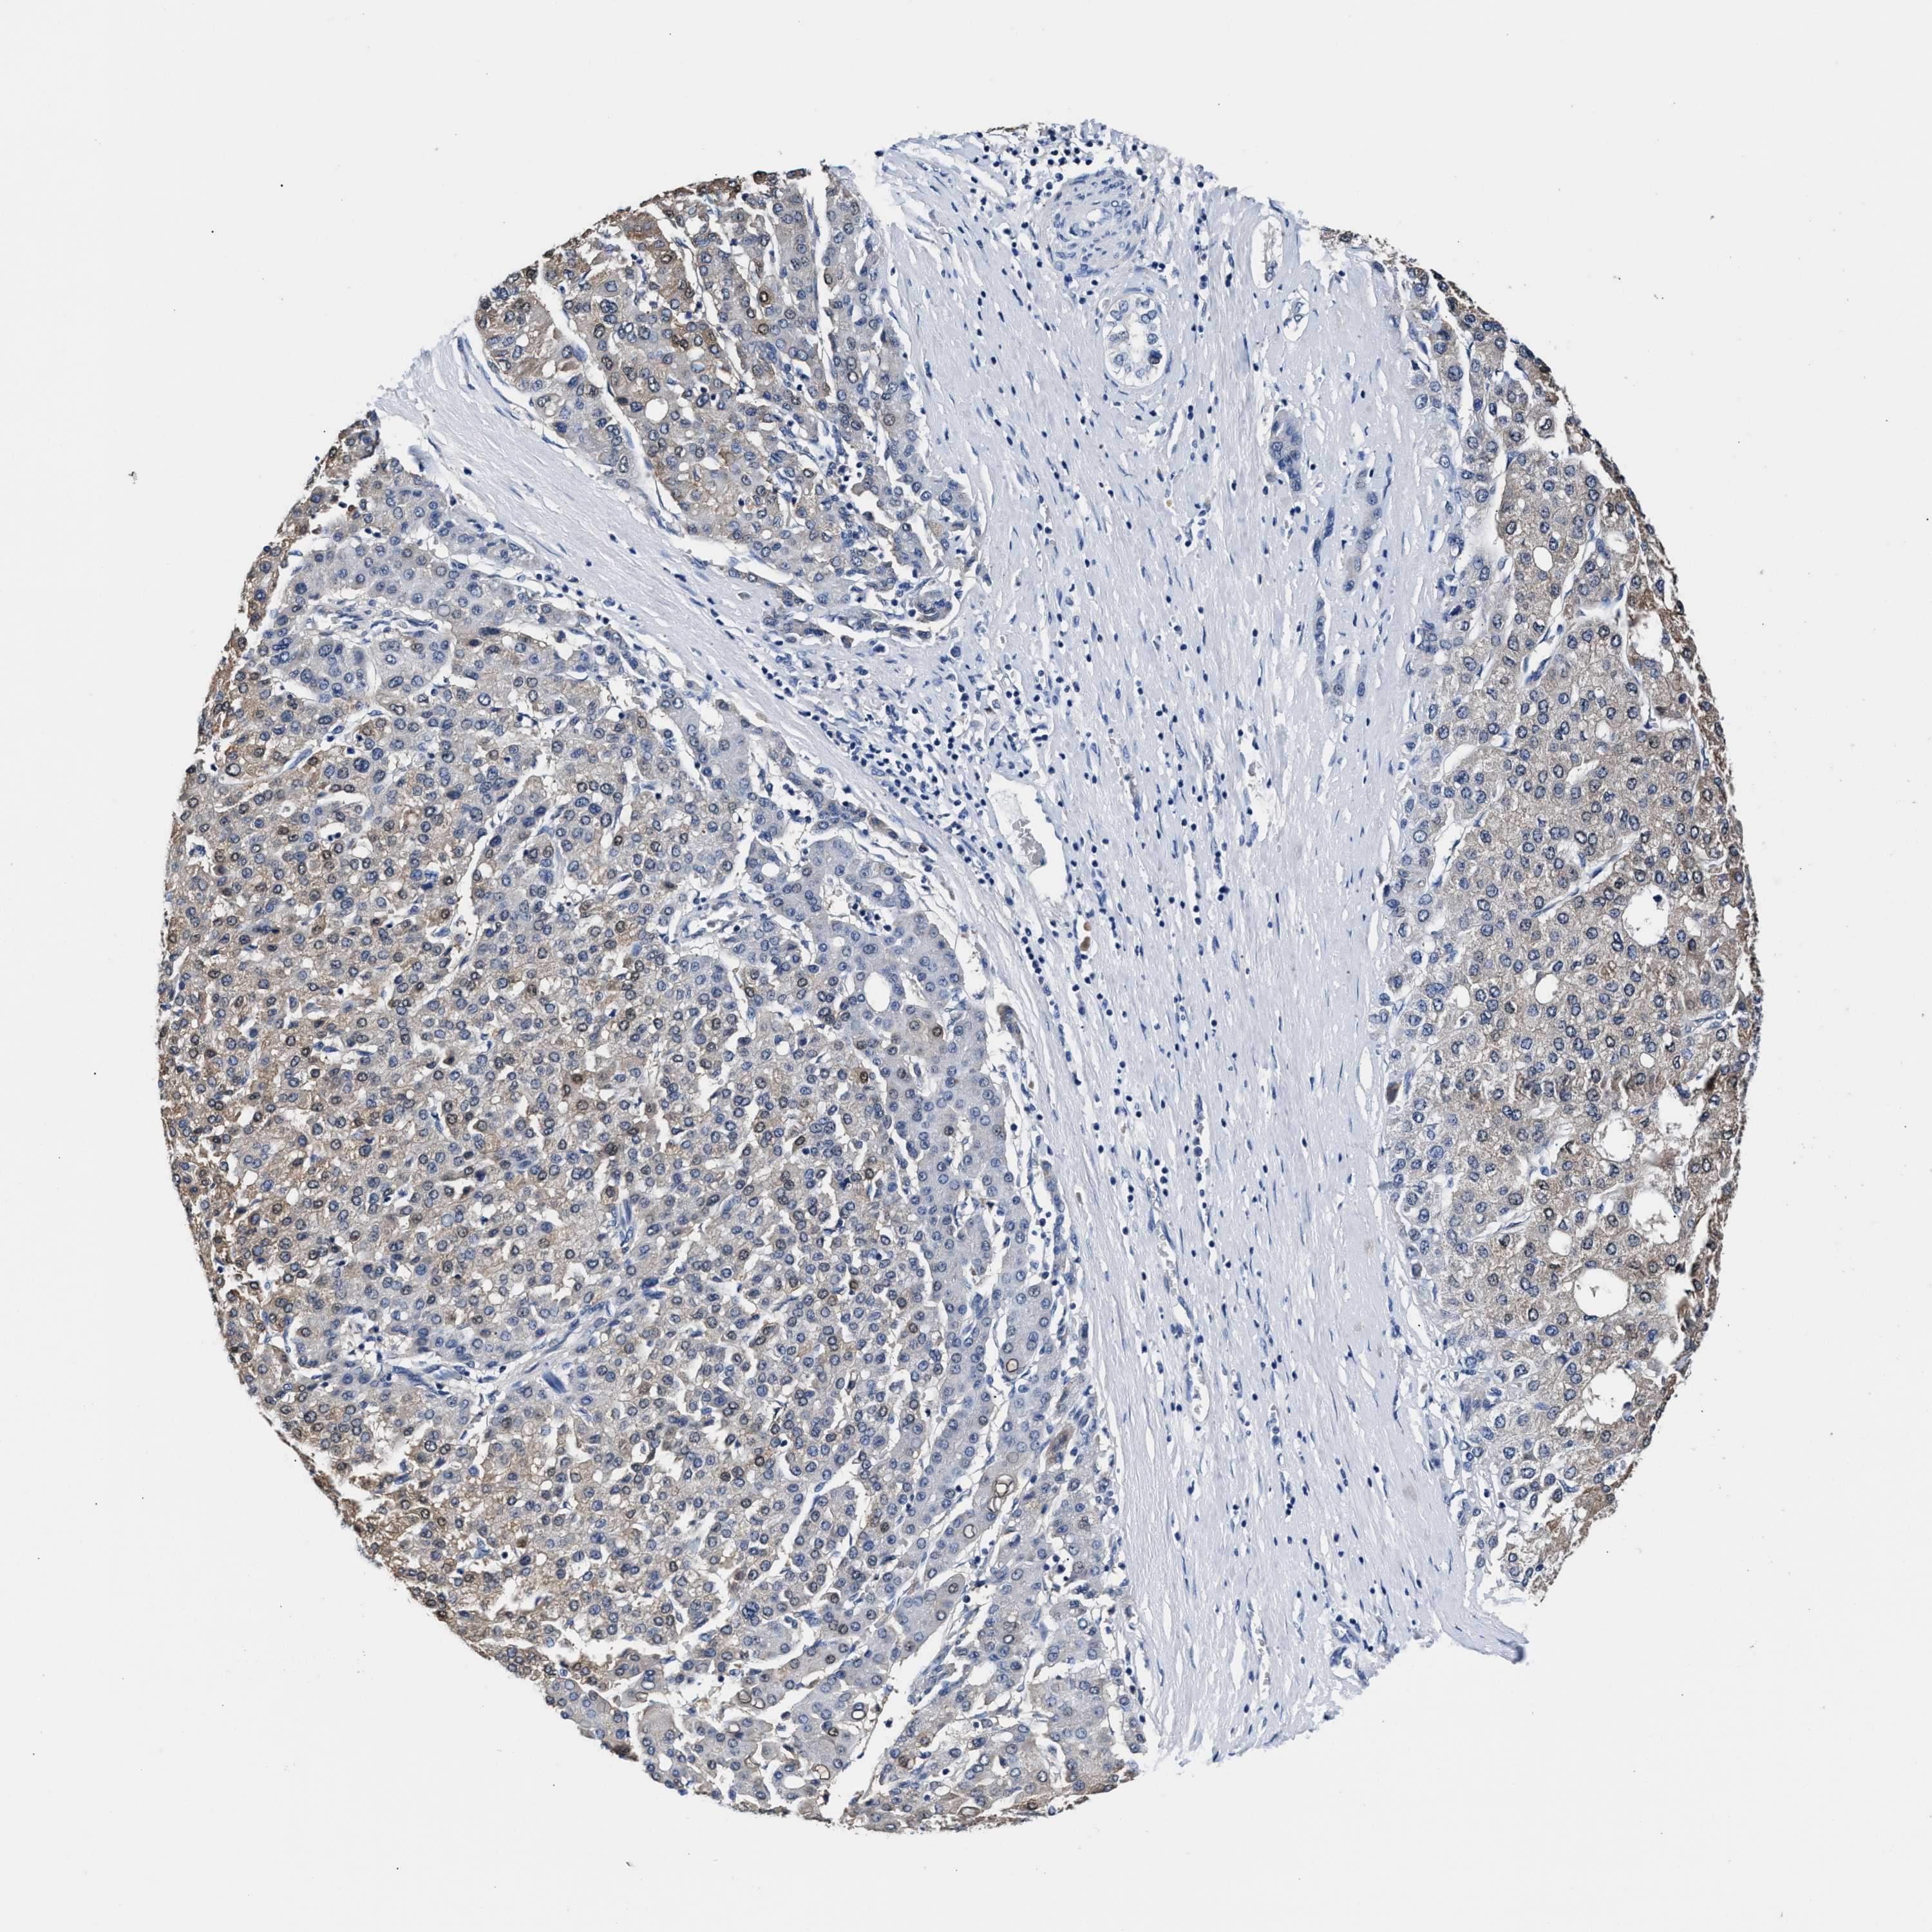

LIVER CANCER - Protein expressioni

A mouse-over function shows sample information and annotation data. Click on an image to view it in a full screen mode. Samples can be filtered based on level of antibody staining by selecting one or several of the following categories: high, medium, low and not detected. The assay and annotation is described here.

Note that samples used for immunohistochemistry by the Human Protein Atlas do not correspond to samples in the TCGA dataset.

Antibody stainingi

Antibody staining in the annotated cell types in the current human tissue is reported as not detected, low, medium, or high, based on conventional immunohistochemistry profiling in selected tissues. This score is based on the combination of the staining intensity and fraction of stained cells.

Each image is clickable and will lead to virtual microscopy that enables deeper exploration of all samples and also displays staining intensity scores, fraction scores and subcellular localization as well as patient and tissue information for each sample.

HPA048652

HPA055972

HPA055973

CAB022669

CAB047357

Staining

High

Medium

Low

Not detected

Intensity

Strong

Moderate

Weak

Negative

Quantity

>75%

75%-25%

<25%

None

Location

Nuclear

Cytoplasmic/membranous

Cytoplasmic/membranous,nuclear

Cholangiocarcinoma

Carcinoma, Hepatocellular, NOS